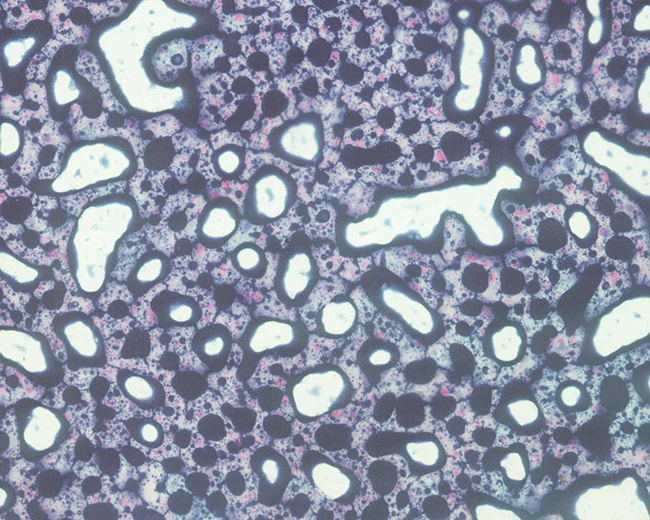

苏丹黑B染色原理 苏丹黑B是一种脂溶性染料,可溶解于脂类中,使细胞内脂类着色而显示出来。对中性脂肪,尤其对磷脂的亲和力更具有特 异性,不仅能显示大的脂肪滴,而且可显示微细结构中的隐性脂类。

阳性产物为黑色或蓝黑色颗粒定位于胞浆中。

粒细胞除原粒细胞外,均可见阳性颗粒,l嗜酸粒细胞呈泡状阳性;单核细胞大多呈弱阳性反应,其颗粒细小,l散在分布; 淋巴细胞、幼红细胞、巨核细胞和血小板呈阴性反应。